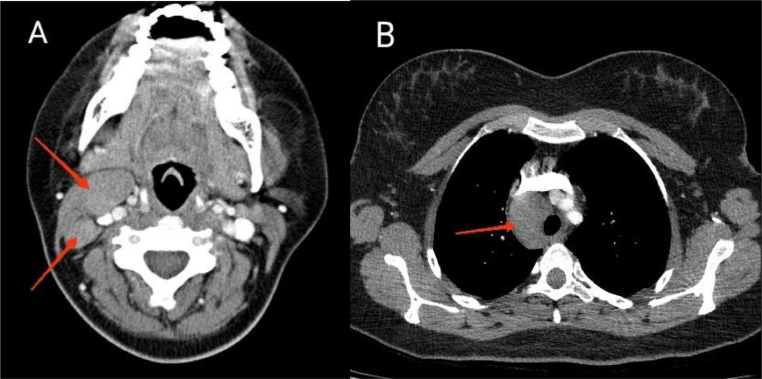

A 27-year-old woman was referred to our center complaining of jaundice and itching a month ago, along with generalized abdominal pain, nausea “non-bloody vomiting,” weakness, and weight loss of 5 kg. She was infected with COVID-19 about 6 months ago and was also treated with prednisolone 5 mg daily since 5 months ago due to subacute thyroiditis. The patient had been using ursodeoxycholic acid “famotidine montelukast hydroxyzine‚” and doxepin prescribed by a general practitioner for itching. She does not drink alcohol and does not smoke, and had no recent trips or family history of liver diseases. Laboratory tests showed an increase in liver enzymes, such as AST 96 U/L (NV < 35)‚ ALT 116 U/L (NV < 35)‚ ALP 1244 U/L (NV < 150)‚GGT 162 U/L (NV < 30)‚ total bilirubin 17.6 mg/dL (NV < 1.2)‚ direct bilirubin 10.6 (NV < 0.2). PT, PTT and INR were normal. The hemogram showed microcytic anemia with increased Ferritin and decreased TIBC (WBC = 4400 Hb = 7.9, MCV = 69.5, Plt = 371,000, Ferritin = 417 [NV = 10-124]‚ TIBC = 197 [250-450]). Thyroid function tests‚ viral hepatitis serologies‚ and other infectious disease panels‚ including HIV‚ CMV‚ and mononucleosis‚ were negative. Serum Ceruloplasmin‚ urine copper level‚ and serum protein electrophoresis were normal. ANA‚ Anti-dsDNA‚ ASMA‚ AMA‚ P-ANCA‚ C-ANCA and anti-LKM-1 were normal. An abdominal ultrasound and spiral CT scan showed multiple small lesions in the spleen and some porta hepatis‚ portocaval ‚and paraaortic lymphadenopathies with maximum SAD = 15 mm (Fig. 1). Due to the lesions seen in spleen and abdominal lymphadenopathies‚ which were suspicious for lymphomatous involvement‚ spiral neck and chest CT scans were performed and showed multiple cervical‚ mediastinal and right paratracheal lymphadenopathies (Fig. 2). The liver and biliary ducts were normal in ultrasound and MRCP.

Fig. 2.

Axial section Neck and Chest CT scan with IV contrast showing (A) Neck and (B) mediastinal lymphadenopathy (red arrows).